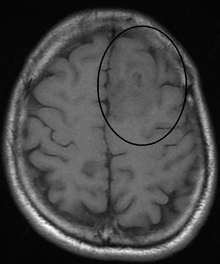

In anywhere from fifty to eighty percent of cases, the first symptom of an oligodendroglioma is the onset of seizure activity. They occur mainly in the frontal lobe. Headaches combined with increased intracranial pressure are also a common symptom of oligodendroglioma. Depending on the location of the tumor, any neurological deficit can be induced, from visual loss, motor weakness and cognitive decline. A computed tomography (CT) or magnetic resonance imaging (MRI) scan is necessary to characterize the anatomy of this tumor (size, location, heter/homogeneity). However, final diagnosis of this tumor, like most tumors, relies on histopathologic examination (biopsy examination).